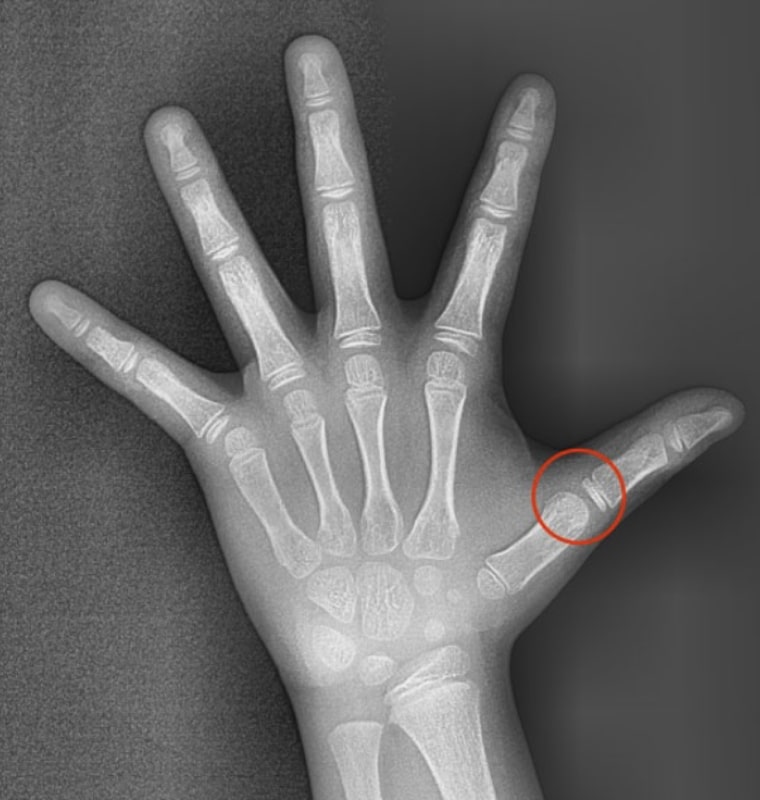

STEP 01 종자골 미출현

종자골 미출현은 성장이 본격화되기 전의 상태로

초기 교정 및 예방적 치료를 시작하기에 적합한 시기입니다.

이 단계에서 적절한 교정 치료를 진행하면 성장기 동안

발생할 수 있는 심각한 부정교합 문제를 예방하고

이후 치료 효과를 극대화할 수 있습니다.